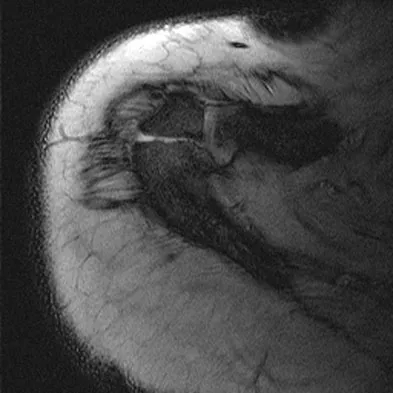

A 23-year-old man reports pain on the superior aspect of his right shoulder with repetitive overhead activities and when lying on his right side. Figure 29 shows an axial MRI scan. What is the most likely diagnosis based on the MRI findings?

Figure 13 shows the MRI scan of a 29-year-old rock climber who reports increasing shoulder pain and weakness. Based on these findings, atrophy will most likely occur in which of the following muscles?